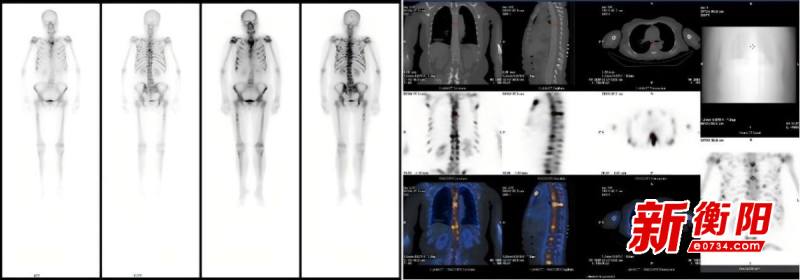

核醫(yī)學(xué)“偵察”破迷霧:南華醫(yī)院揪出隱匿的急性白血病

近日,南華大學(xué)附屬南華醫(yī)院核醫(yī)學(xué)科通過層層抽絲剝繭,成功為一位72歲女性患者揪出病因,為患者爭(zhēng)取了寶貴的治療時(shí)機(jī)。